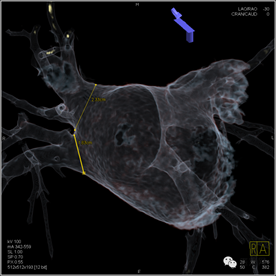

术前:测量肺静脉直径

左上肺静脉造影及融合

影像融合下用于冷冻球囊的定位